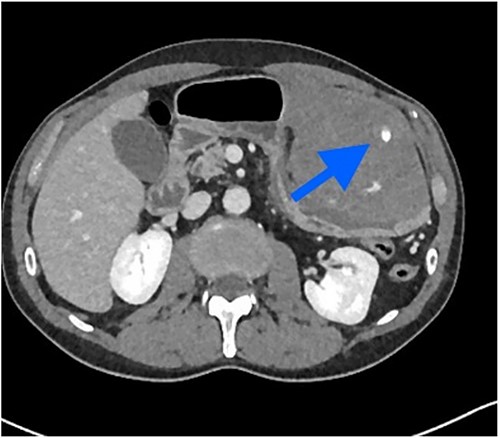

The patient was pale, hemodynamically stable, and with signs of peritoneal irritation. His hemoglobin was 15.1 g/dL. Contrast enhanced CT demonstrated 11.6 × 8.8 × 16.5 cm3 intramural hematoma in anterior stomach wall with active bleeding and hemoperitoneum (Figs 2 and 3). Exploratory laparotomy was done after optimizing the patient.